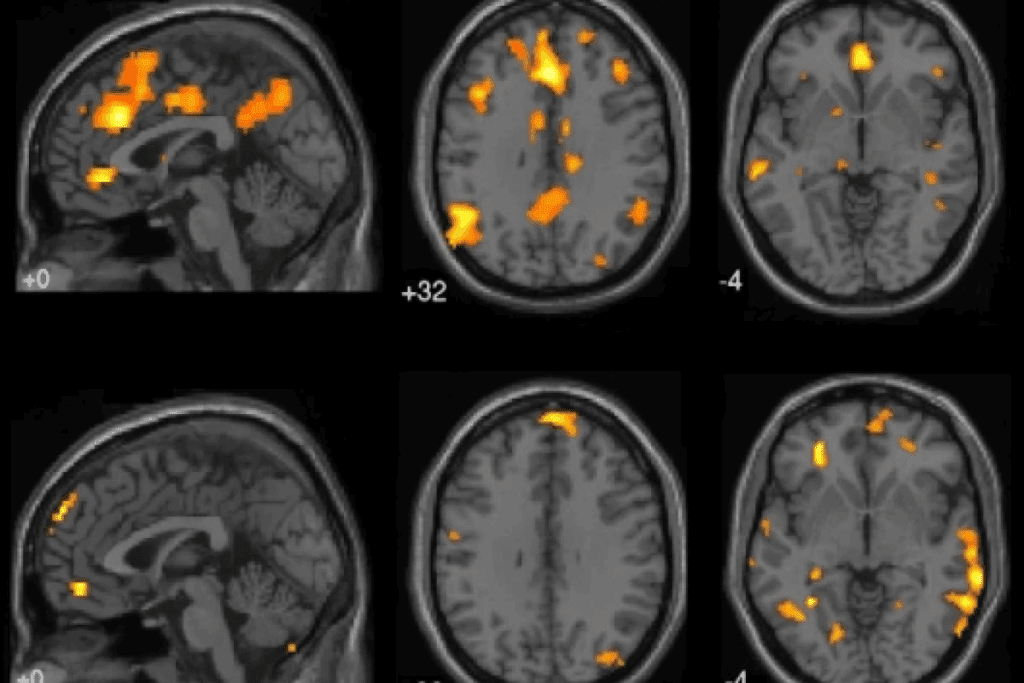

Neuroimaging Techniques

Neuroimaging is vital for spotting brain metastases. Magnetic Resonance Imaging (MRI) is top for this job. It shows brain details clearly and finds metastases well.

Computed Tomography (CT) scans are also used. They’re quick and help in emergencies. Though not as good as MRI for small spots, they’re useful for bigger ones and related issues.